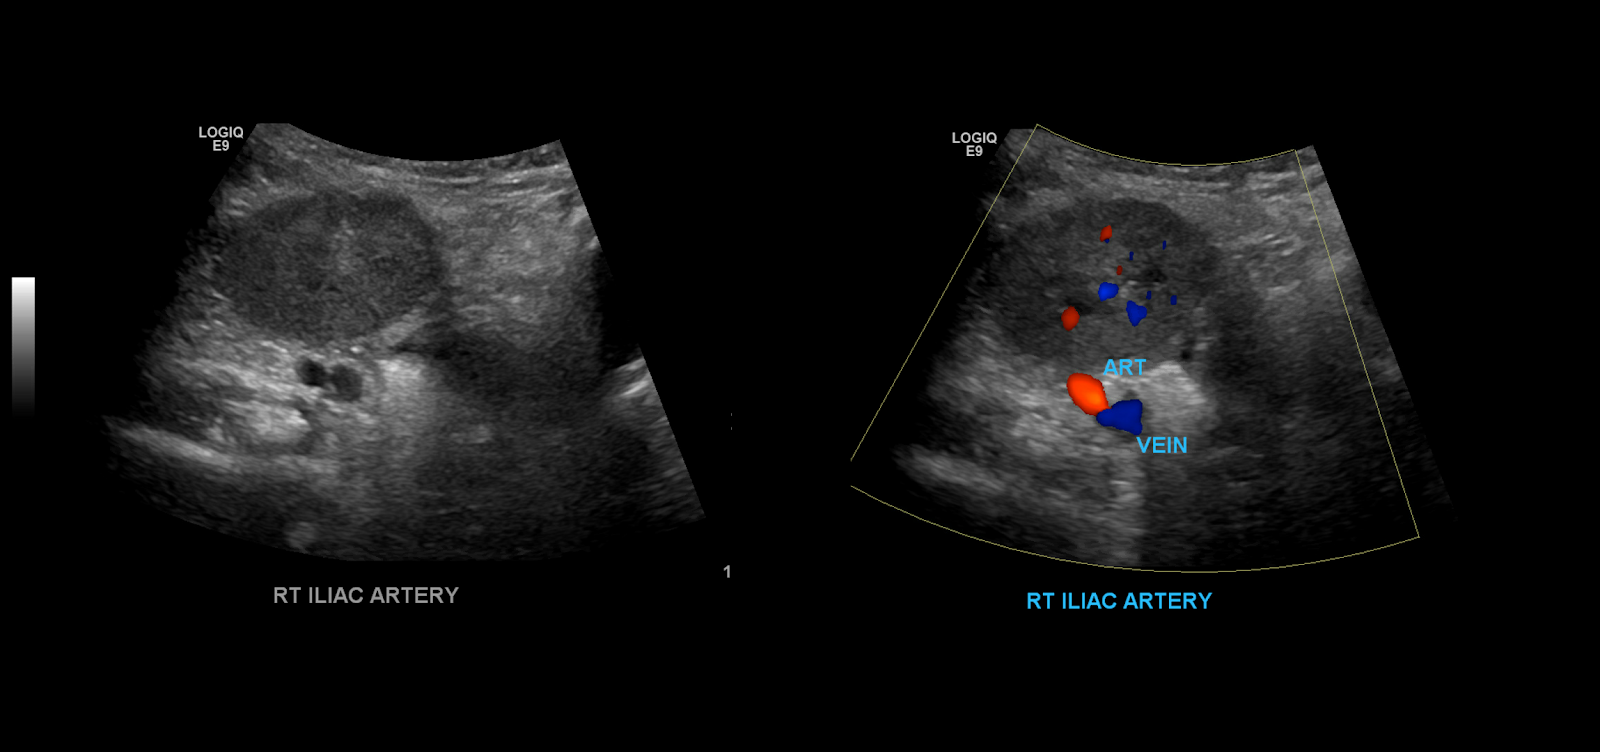

When you’re done examine the kidney in gray-scale you become to take your color spectral Doppler images. Begin with the iliac vessels.

Take gray-scale, color and spectral Doppler of the common iliac artery. Use angle correction 45-60°.

Measure the peak systolic and end diastolic velocities.